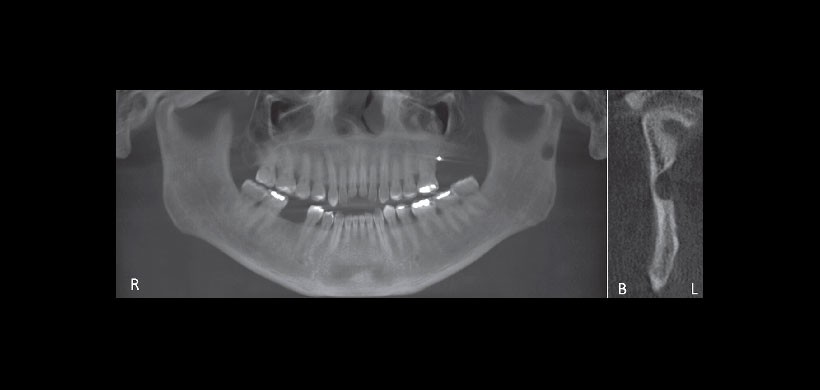

Fig 2. Tomografía computarizada de haz cónico. Reconstrucción panorámica y vista muestran la depresión cortical bien en la rama. Tenga en cuenta la ubicación lingual de la concavidad.